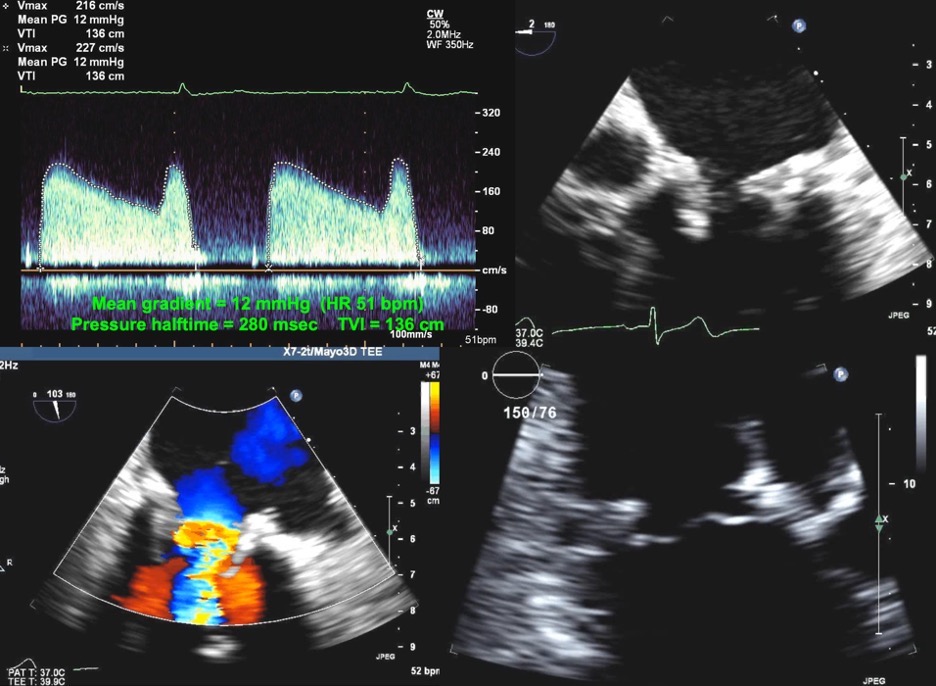

Fig. 6.Correct and Incorrect method of measuring the TVI of the LVOT. Top Images: Pulse Wave Doppler with sample volume placed immediately proximal to the zone of flow acceleration within the LVOT, with an accurate TVI of 27 cm. Bottom images: Pulse Wave Doppler with sample volume placed within the zone of flow acceleration leading to a spuriously elevated TVI of 38 cm. This can lead to an elevated DVI in a patient with an obstructive prosthesis, and care should be taken to avoid this error.